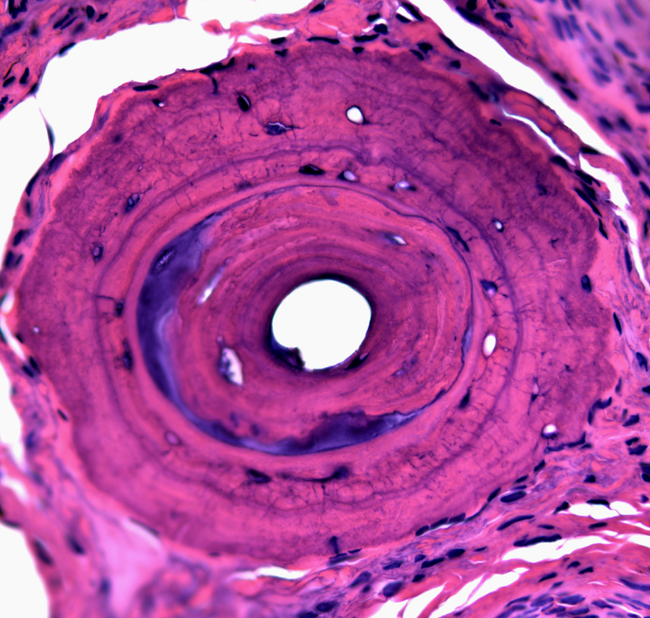

Have a look at some image samples our faculty has captured using the scanning electron microscopes (SEM), transmission electron microscopes (TEM), and light microscopes (LM) in the Advance Microscopy Facility (AMF).